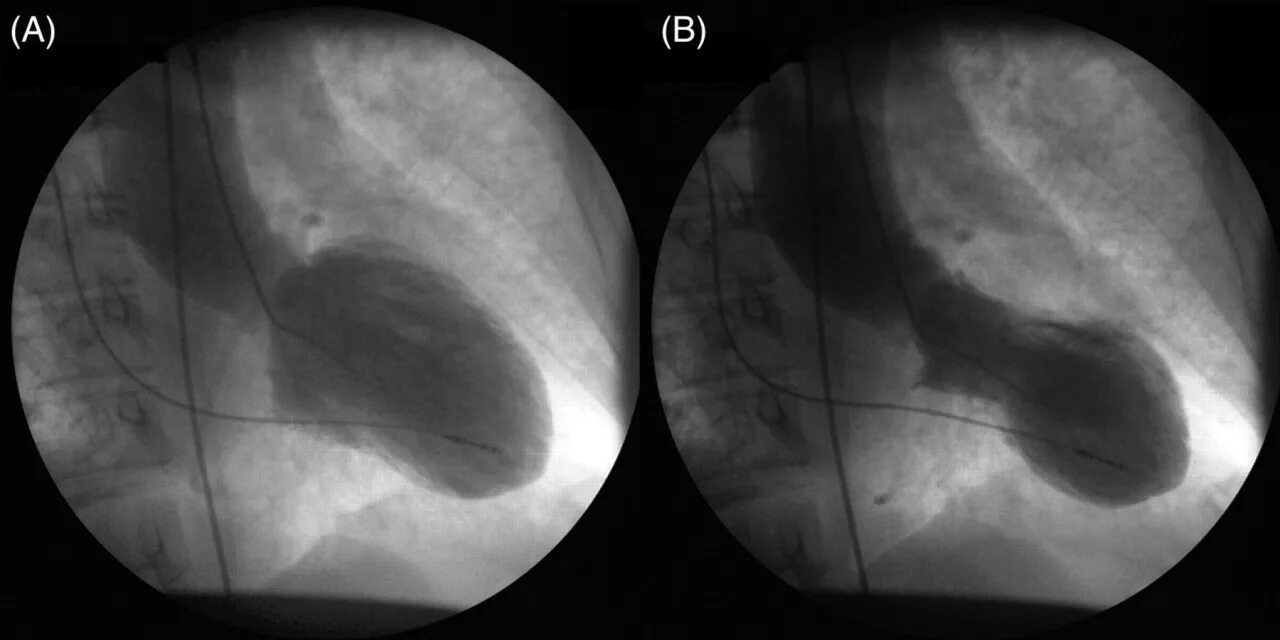

Синдром разбитого сердца симптомы